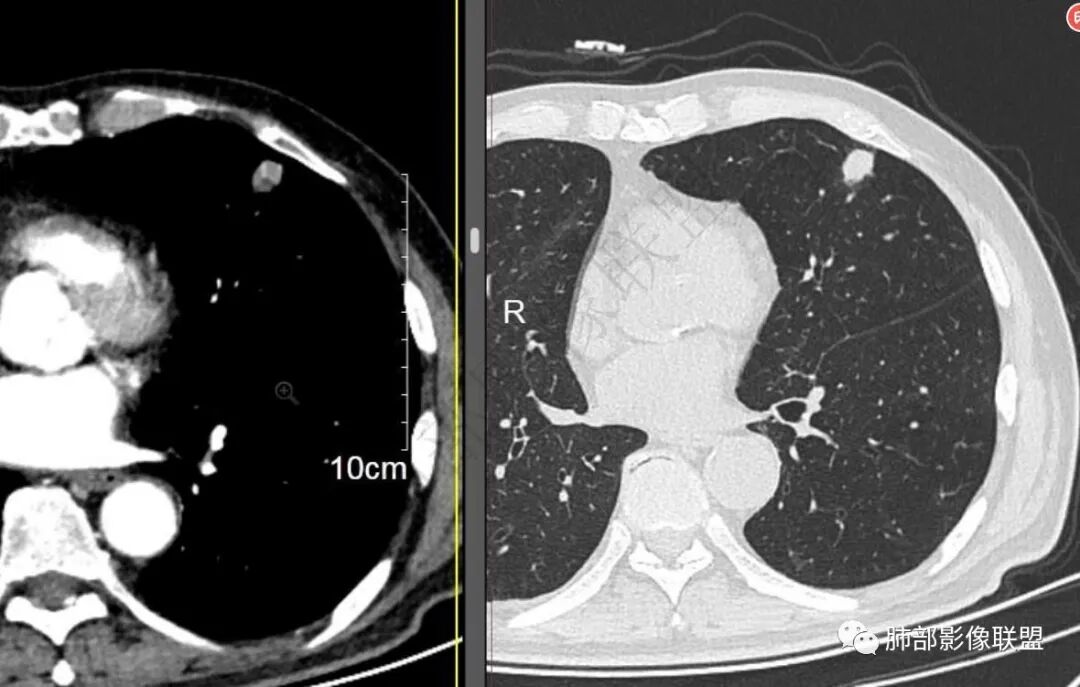

二..发现左肺上叶舌段实性密度小结节影,不规则略呈半环形,边界清楚,未见分叶、毛刺及磨玻璃晕。未见卫星病灶。

9个月后病灶明显增大,边缘较平直,部分膨隆,锁扣样外观,仍旧缺乏典型深分叶及张力,未见胸膜凹陷。

再1个多月后病灶继续增大,较明显不均匀强化,肺门一侧见低密度区。病灶边缘相对不清,可见毛刺。